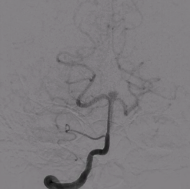

基底动脉闭塞患者接受机械取栓治疗前后对比图